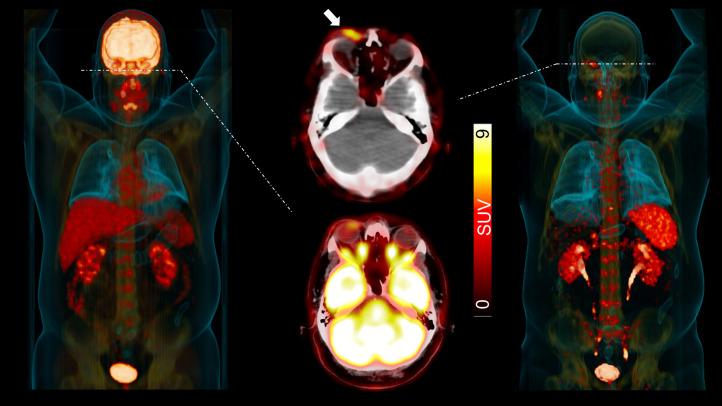

In the early 2000s, major clinical trials provided evidence of a favorable outcome from antibody-mediated radioimmunotherapy for hematologic neoplasms, which then led to Food and Drug Administration approval. For instance, the theranostic armamentarium for the referring hematooncologist now includes Y-ibritumomab tiuxetan for refractory low-grade follicular lymphoma or transformed B-cell non-Hodgkin lymphoma, as well as I-tositumomab for rituximab-refractory follicular lymphoma. Moreover, the first interim results of the SIERRA phase III trial reported beneficial effects from the use of I-anti-CD45 antibodies (Iomab-B) in refractory or relapsed acute myeloid leukemia. During the last decade, the concept of theranostics in hematooncology has been further expanded by C-X-C motif chemokine receptor 4-directed molecular imaging. Beyond improved detection rates of putative sites of disease, C-X-C motif chemokine receptor 4-directed PET/CT also selects candidates for radioligand therapy using β-emitting radioisotopes targeting the identical chemokine receptor on the lymphoma cell surface. Such image-piloted therapeutic strategies provided robust antilymphoma efficacy, along with desired eradication of the bone marrow niche, such as in patients with T- or B-cell lymphoma. As an integral part of the treatment plan, such radioligand therapy-mediated myeloablation also allows one to line up patients for stem cell transplantation, which leads to successful engraftment during the further treatment course. In this continuing education article, we provide an overview of the current advent of theranostics in hematooncology and highlight emerging clinical applications.

在 21 世纪初,几项大型临床试验为血液系统恶性肿瘤的抗体介导的放射免疫治疗提供了有利结果的证据,随后获得了食品和药物管理局的批准。例如,现在,血液肿瘤学家的治疗武器库包括用于难治性低级别滤泡淋巴瘤或转化 B 细胞非霍奇金淋巴瘤的 Y-碘替比单抗替曲膦,以及用于利妥昔单抗难治性滤泡性淋巴瘤的 I-替西莫单抗。此外,SIERRA 三期试验的首次中期结果报告了使用 I-抗-CD45 抗体(Iomab-B)治疗难治性或复发性急性髓系白血病的有益效果。在过去十年中,血液肿瘤学中的治疗学概念通过 C-X-C 基序趋化因子受体 4 定向分子成像得到了进一步扩展。除了提高潜在疾病部位的检测率外,C-X-C 基序趋化因子受体 4 定向 PET/CT 还选择了使用针对淋巴瘤细胞膜上相同趋化因子受体的 β 发射放射性同位素进行放射性配体治疗的候选者。这种基于图像的治疗策略提供了强大的抗淋巴瘤疗效,并期望消除骨髓龛,例如在 T 或 B 细胞淋巴瘤患者中。作为治疗计划的一个组成部分,这种放射性配体治疗介导的骨髓清除也允许患者进行干细胞移植,这导致在进一步的治疗过程中成功植入。在这篇继续教育文章中,我们概述了血液肿瘤学中治疗学的当前发展,并强调了新的临床应用。